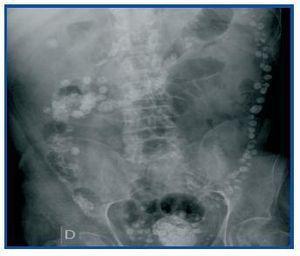

Dear Editor, Lanthanum carbonate is a calcium and aluminium-free phosphorus binder that has recently come to market in Spain. It is a heavy, non-toxic metal that is not absorbed by the intestine. The substance’s package leaflet in our country does not allude to the phenomenon of its appearance in radiology images. This is not the case in the USA’s version, which states that “radio-opaque images may appear in abdominal radiographies of patients who consume lanthanum”.1 The most commonly reported adverse reactions were gastrointestinal, but the clinical trials did not include patients with intestinal obstructions or inflammatory intestinal disease.2 We present the case of a 58-year old man with pan-colonic diverticulosis and frequent diverticulitis episodes with CKD secondary to diabetic nephropathy who began a periodic haemodialysis programme in April 2001. He was admitted in July 2008 for fever and abdominal pain. An emergency abdominal CT ruled out signs of diverticulitis, but the radiologist reported “remnants of contrast in the entire colon and terminal ileum” (figure 1), which was confirmed by a simple abdominal x-ray (figure 2). Our patient had not received any radiological contrast at any time, but he had been receiving treatment with 3000mg lanthanum carbonate daily for severe hyperphosphataemia since February of that year, with excellent lab results and good clinical tolerance up to that moment. The final diagnosis was sepsis due to Enterococo avium, most likely of intestinal origin. Since there were no other findings in the imaging tests that could explain the abdominal pain, lanthanum treatment was discontinued, after which the patient remained asymptomatic. With a view to studying the findings, a simple abdominal radiograph was taken in another patient receiving the same dose of that metal and who had not had any digestive symptoms. The deposit was also observed throughout the contour of the colon, but showed a different radiological pattern (figure 3). References in the literature describing this phenomenon are scarce and contain various explanations. According to our research, the first radiological image attributed to lanthanum consumption was shown by Cerny and Kunzendorf3 in 2006. In this case, the drug was discontinued because after seeing the radiography, doctors felt that the patient’s abdominal pain could be related with the lanthanum. Other cases were subsequently reported.4 David et al.5 interpreted the radiograph as an intestinal deposit of calcium phosphate stones that prove lanthanum’s effectiveness as a binder, and even suggest that such an image could be used as a test of therapeutic compliance. That theory is refuted by Pafcugova et al.,6 who showed that the tablets themselves inside a vial are radio-opaque, in absence of calcium or phosphorus. However, given our limited experience with the use of this drug, particularly in Spain, it is still not clear what the radiographical distribution pattern is in the abdomen, or whether it can be observed in all patients receiving this medication. Vrigneaud et al.7 studied 13 patients treated with lanthanum. In six, the abdominal radiograph is completely normal, while in the rest, the radioopaque deposit may be observed. However, in contrast with the habitual images with opaque areas smaller than one centimetre distributed regularly throughout the contour of the colon, we found two cases in which the areas were larger and irregularly distributed along the digestive tract. These were in one patient who did not chew the tablets correctly, and another patient with colonic diverticulosis whose profile suggests the material was deposited in the diverticuli, as with the present case. Our conclusion is that although little data exists about the radiological behaviour of intestinal lanthanum carbonate deposits, it is necessary to know that it is radio-opaque. Furthermore, it is likely that the drug should be used cautiously in patients with intestinal diseases. In addition, we do not know its elimination time, which is crucial information when it comes to performing other imaging studies without interferences. And lastly, we believe that all of the above should be included in the drug’s technical leaflet printed in Spain.

Figure 2. Simple abdominal radiography without contrast showing multiple onecentimetre sized opaque points irregularly distributed along the contour of the colon, which are lanthanum deposits in the diverticuli.